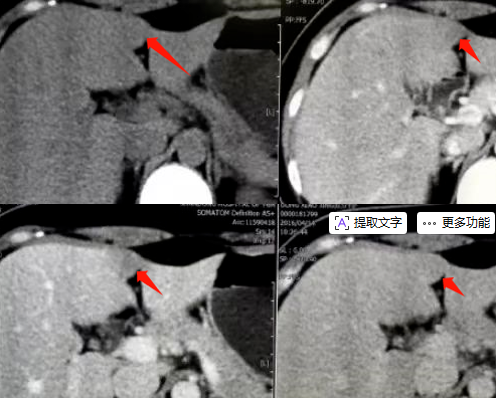

肝脏CT平扫:肝左内叶、左外叶镰状韧带旁可见斑片状低密度影,边界清,长径约1.5cm。

肝脏MR平扫及增强:肝左内叶及左外叶镰状韧带旁可见斑片状稍长T1、等T2信号,长径约1.6cm,病灶于T1WI反相位较同相位信号减低,增强各期均呈低信号表现。脾脏增大。

影像表现:病灶多较小,最大径通常小于2.5cm,可为不规则形、类圆形或三角形。根据平扫及增强扫描图像上的密度及其变化情况,将其分为A型和B型。

A型:占大多数,平扫呈等密度 ,动脉期呈等密度或略低密度,门脉期呈低或稍低密度且门脉期显示最清晰,平衡期及延迟扫描呈等或略低密度。(见下图所示)

B型:平扫、各期增强均呈低或略低密度。(见下图所示)